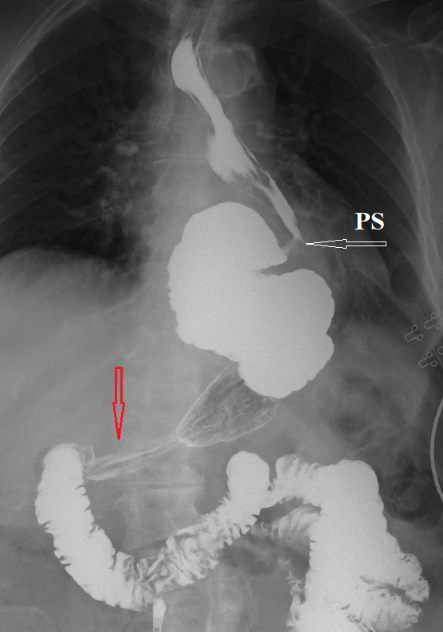

Figure 2. An 84-year-old female patient underwent Nissen fundoplication for GERD. She suffered from severe and frequent heartburn. Two attempts to perform gastroscopy were unsuccessful due to a large amount of food in the esophagus. The X-ray in the vertical position shows an S-shaped esophagus filled with barium between the LES and the proximal sphincter (PS). The red arrow shows contraction of the antrum because of antral gastritis. Evacuation of the contrast agent is not impaired. Since taking PPI did not help with heartburn, she was “saved” by milk. Only drinking a glass of milk relieved the heartburn. She did not know that the next attack of pain was caused by drinking milk. Refusal of milk significantly improved her symptoms.

In the literature, without any evidence, the opinion is spread that with milk intolerance, it is necessary to reduce its volume to a level where no symptoms appear. This is explained by the fact that lactose is supposedly necessary for the absorption of calcium [11]. Firstly, it is known that GERD progresses for a long period without clinical manifestations. Therefore, the absence of symptoms does not exclude the effect of lactose to cause hypersecretion of hydrochloric acid and progression of the disease. Secondly, even a small amount of milk in a cup of coffee causes hypersecretion of hydrochloric acid, which manifests itself as heartburn. Thirdly, as shown above, a lactose-free diet outside of breastfeeding does not harm people's health. Therefore, to prevent the progression of GERD, I recommend refusing to take products containing lactose.